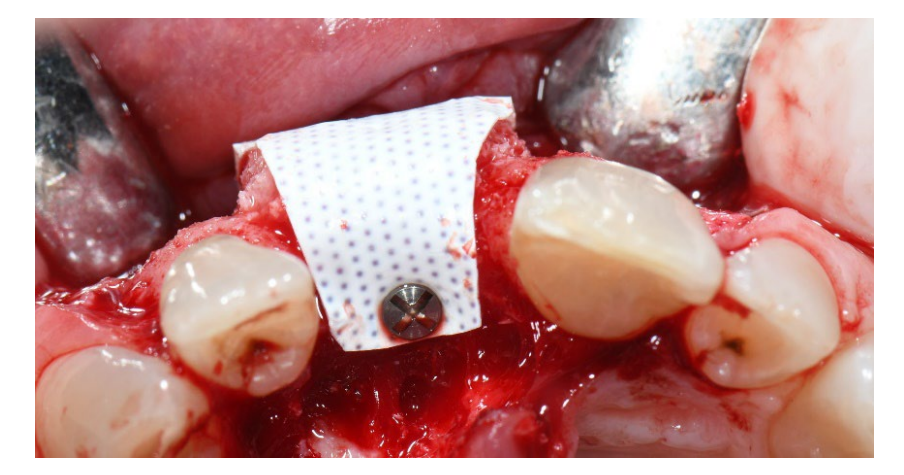

In group A, socket preservation with intentionally exposed non-resorbable d-PTFE membrane (test group, Figures 1–4), the residual alveolar socket was grafted with porcine-derived cancellous anorganic bone material (0.25–1 mm particles, Zcore, DeOre s.r.l., Negrar [Vr], Italy). Then, a non-resorbable, dense-polytetrafluoroethylene (d-PTFE) membrane (Cytoplast TXT1224, DeOre) was shaped according to the dimension of the residual socket, and it was inserted into a buccal and lingual pocket. Finally, a horizontal mattress suture (Cytoplast PTFE Suture 4-0, DeOre) was placed to secure the membrane and stabilize it to the soft tissue margins. The application of the non-resorbable d-PTFE membrane did not require primary closure via buccal flap advancement. The sutures were removed between 10 and 14 days post-surgery, and the non-resorbable d-PTFE membrane was removed between the fourth and the fifth weeks after surgery. After that, the wound was left to heal for about five months, allowing by the process of re-epithelialization.